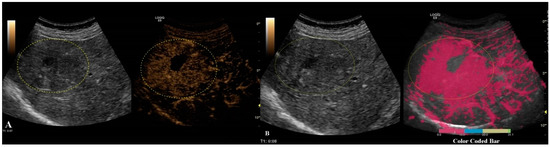

The first step was to exclude or confirm liver cirrhosis (F = 4) by measuring liver stiffness (LS). It was possible to complete this step by using the 2D-SWE.GE technique offered on a LOGIQ E9 scanner with a C1-6-D probe [7] or by using vibration-controlled transient elastography (VCTE), using the M and XL probes (FibroScan®, Echosens, Paris, France) [8]. The measurements were performed according to the EFSUMB guidelines for liver elastography [9]. All of the patients that were evaluated in our department for liver lesions were, by default, screened for liver fibrosis via non-invasive means; thus, this information could be found in the patients’ files (Figure 2).

Figure 2. In frame (A), we have depicted a cirrhotic liver evaluated by the 2D-SWE.GE technique, where the color-coded map points out a reddish color, compared with frame (B), where the color-coded map depicts a blue color, meaning the absence of fibrosis.